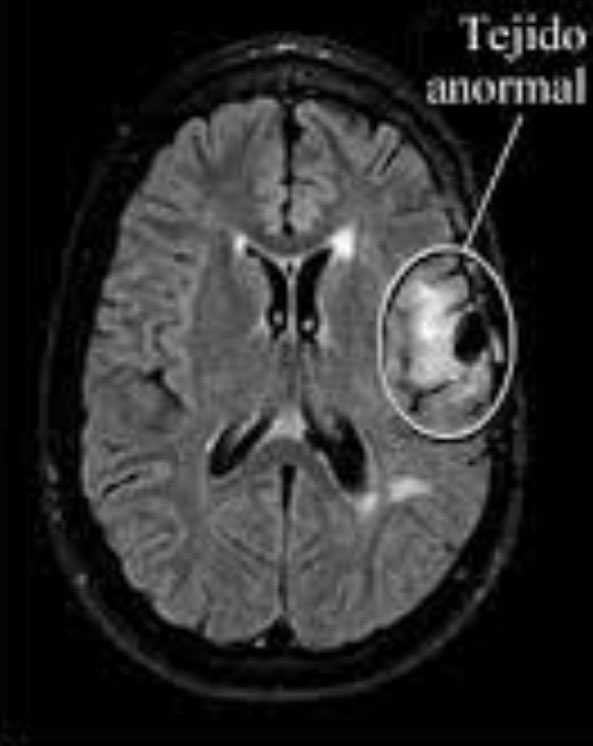

Las neuroimágenes son fundamentales para clasificar las epilepsias según etiologías o causas. La Resonancia Nuclear Magnética de Cerebro (RNM) es el «standard de oro», pero debe realizarse con un protocolo especial para epilepsia. Permite diagnosticar malformaciones, alteración de la migración neuronal, tumores y/o secuelas de enfermedades infecciosas como meningitis, encefalitis, entre otras causas.

Resonancia nuclear Magnética cerebral, que muestran tejido normal (figura 1) y tejido anormal (provocado por una lesión) que puede causar crisis epilépticas (figura 2).